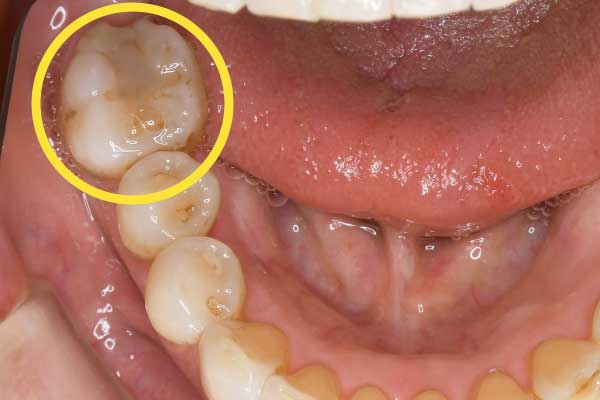

| 主訴 | 奥歯にインプラントが必要と言われたが、どうしても避けたい |

|---|---|

| 治療内容 | 親知らずを活用した矯正治療 |

| 治療期間 | 準備中 |

| 治療費 | 準備中 |

| 治療の リスク | 矯正で動かす場合、数ヶ月〜数年の時間がかかる。治療中の装置により汚れが溜まりやすく、虫歯や歯周病のリスクが高まる。 |

こちらの患者様は、すでに奥歯を抜歯しており、「噛む機能を回復するにはインプラントしかない」と宣告されていました。

しかし、「手術が怖い」「体に人工物を入れることに抵抗がある」という強い思いから、インプラント以外の方法を模索して当院へお越しになりました。

通常、歯を失った場所にはインプラントやブリッジを検討しますが、当院では「親知らずを矯正装置で奥に移動させ、抜けた奥歯のスペースを埋める」という治療を行いました。